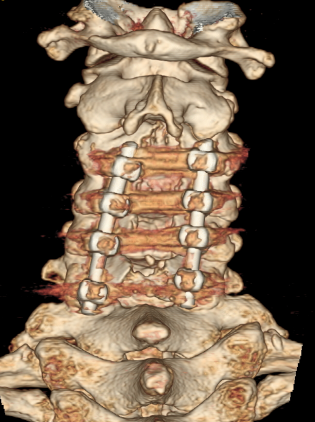

术后CT见减压充分,螺钉位置良好